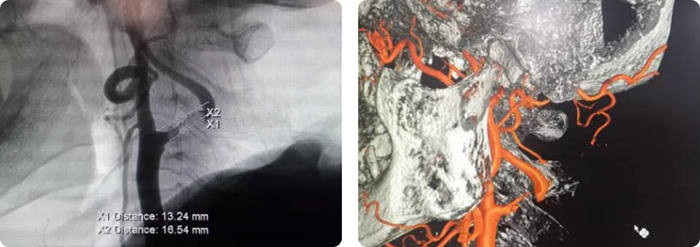

术前影像

术后复查CTA与术前对比图